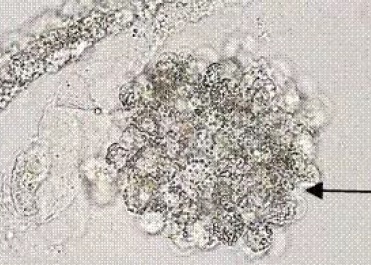

A, :肾小管上皮细胞